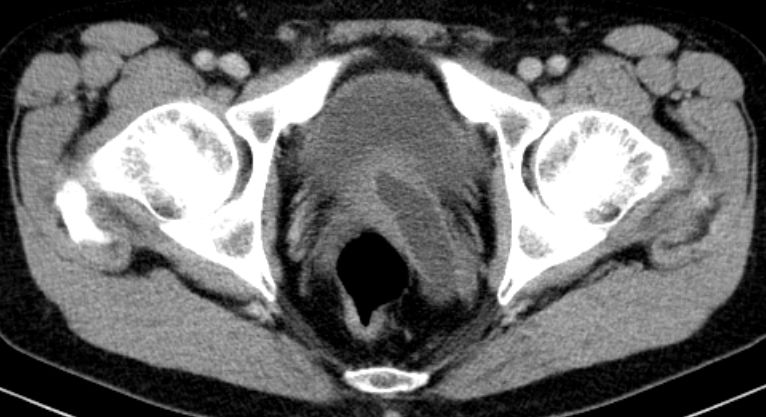

Der stark dilatierte Ureter links im kleonen Becken.

Ungewöhnlich Einmündung des dilatierten Ureters durch die Prostata in die Blase.